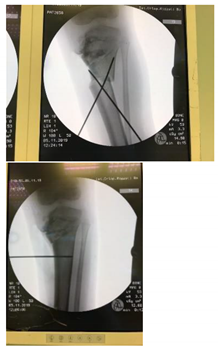

The CASS process was achieved agreeing to the surgeons’ likings and experiences; thus, patients were not consecutive and the study was not randomized. Parents and carers provided authorization for the study. The methodology described and illustrated by the example of a Monteggia lesion has been applied to all the cases reported in Table 4. This resulted in seven different assembly files on CREO, each one representing the phases of the respective surgery. Applying simulation to more than one pathology, involving different body segments, has enabled its effectiveness to be verified and the problems to be solved or improved. Some of the cases have already been operated and the surgeons of Rizzoli were very satisfied with the results obtained in the pre-operative planning phase, finding a considerable reduction in risks and timing during the operating phase.

The simulation results in a three-dimensional model presenting the anatomical group after the operation (Scheme 1). On it can be detected all the necessary measures in the pre-operative planning phase and the program also allows saving the file in many different types of formats so that it is exportable to other software and not viewable only by CAD.

The literature has documented the error that is made by carrying out this type of measurement on two-dimensional images, an extremely limiting procedure that easily provides inaccurate results. It is therefore necessary to obtain these quantities with the maximum possible accuracy, since a difference of a few degrees of correction determines appreciable variations in the performance of the intervention [32].

Being able to rely on these tools leads to an improvement in the clinical outcome, lower risks for the patient and reduced post-operative recovery times; the R.X. exam is not performed, with a consequent decrease in the patient’s exposure time to X-rays, plus, the reduction in the timing of the intervention allows a lower anesthetic dose for the patient. This method is particularly advantageous because it allows surgeons to evaluate, before surgery even, which surgical accessories are best suited to the specific anatomical geometry, as shown in the case of femur afflicted with Ollier syndrome. The dimensions of screws, plates and other surgical supports are defined in the catalog and, following the traditional practice, the surgical room must be equipped with a wide variety of tools to be able to meet any need; to be able to decide in advance the dimensions of the screws that realize the desired support allows even more reductions in the times and the risks associated with the intervention, as well as to greatly limit the dimensions in the operating room.